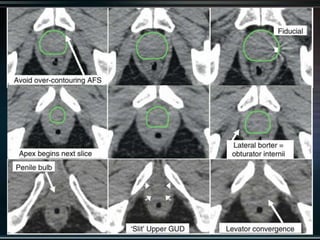

Delineation

Our unit decide to treat:

 Prostate + S.V & prophylactic Pelvic LNs in

phase1

 Prostate + S.V phase 2

 Delineation of our unit illustrated in the

following slides:

Our unit decideto treat:  Prostate + S.V & prophylactic Pelvic LNs in phase1  Prostate + S.V phase 2  Delineation of our unit illustrated in the following slides: